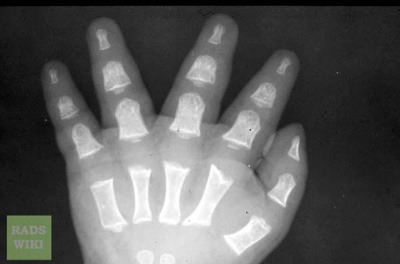

There is no major treatment for this disease. Like abnormalities, it should be attempted to be treated when causing major problems.